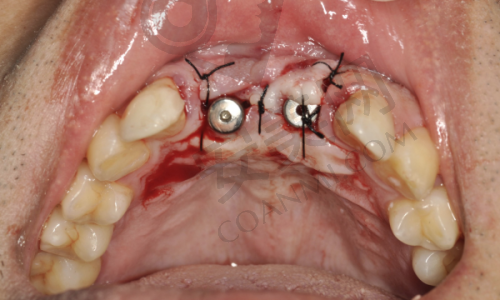

确定好种植方案后,医生就安排我进行种植牙手术。在手术前,护士为我进行了口腔消毒和局部麻醉。麻醉生效后,我并没有感觉到明显的疼痛。手术过程中,医生和护士都非常专精和细心,他们密切配合,操作熟练。我能感觉到医生在小心翼翼地进行每一个步骤,虽然我有些紧张,但医生时不时地跟我交流,安慰我,让我放松了不少。整个手术过程大约持续了一个多小时,手术非常顺利。术后,医生向我交代了一些注意事项,比如要注意口腔卫生,避免食用实力强的食物等。

手术后的几天里,我的口腔有一些轻微的肿胀和疼痛,这是正常的术后反应。我按照医生的嘱咐,按时服用消炎药和止痛药,并且注意饮食和口腔卫生。在修复期间,医院的医生还会定期打电话回访我,了解我的修复情况,并给予我专精的指导和建议。随着时间的推移,肿胀和疼痛逐渐减轻,大约一周后,我的伤口就基本愈合了。在接下来的几个月里,种植体与牙槽骨逐渐结合,我也能明显感觉到口腔的功能在逐渐修复。